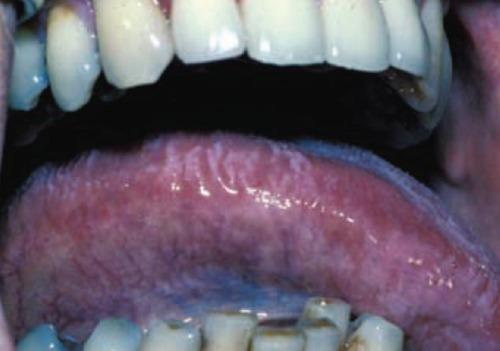

在首次被描述近30年后,艾滋病毒仍然是一种全球大流行病。本文旨在综述目前关于艾滋病毒感染的耳鼻喉(ENT)表现的知识,并介绍现有的诊断和治疗选择。在Medline和其他可用的数据库来源中进行了文献综述。数据分析中还纳入了相关书籍中的信息。众所周知,高达80%的艾滋病毒感染患者最终会出现耳鼻喉表现;其中,口腔疾病似乎最为常见。口咽表现包括念珠菌病、牙周和牙龈疾病、单纯疱疹病毒和人乳头瘤病毒感染、口腔毛状白斑、卡波西肉瘤和非霍奇金淋巴瘤。颈部的耳鼻喉表现可表现为颈部淋巴结病或腮腺肿大。相应的鼻部表现包括鼻窦炎(通常由非典型细菌引起)和过敏性鼻炎。最后,耳部表现包括中耳炎(外耳炎或中耳炎)、内耳受累(感音神经性听力损失、平衡失调)和面神经麻痹(与普通人群相比频率高达100倍)。虽然耳鼻喉症状不能诊断该疾病,但它们可能提示艾滋病毒感染,或与其进展及相应的治疗失败有关。耳鼻喉科医生应了解与艾滋病毒疾病相关的耳鼻喉表现以及相应的诊断和治疗方法。可能需要采取多学科方法为艾滋病毒患者提供适当水平的护理。